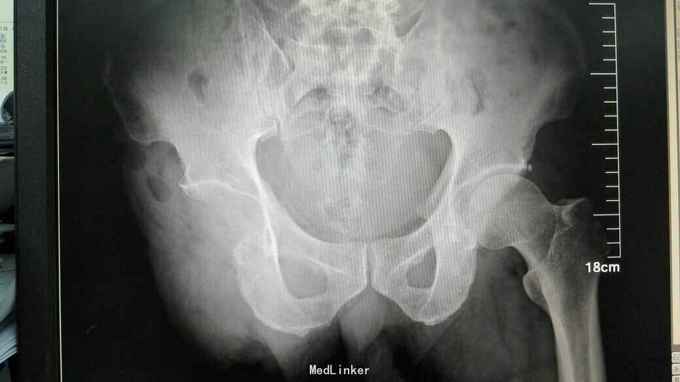

随访半年后肿瘤局部复发,再次行PET-CT检查排除远处转移后行右侧半骨盆离断术,目前术后3月,恢复良好,暂未见复发和转移 讨论:滑膜肉瘤为恶性程度很高的软组织肿瘤,局部复发率高,远处最易出现肺转移,文献报道5年生存率仅20%~40%。由于滑膜肉瘤对放化疗不太敏感,手术切除为目前最有效治疗手段,所以手术应尽可能切除干净,手术范围应该包括切除肿瘤所在间室肌肉全部,从而减少术后复发。